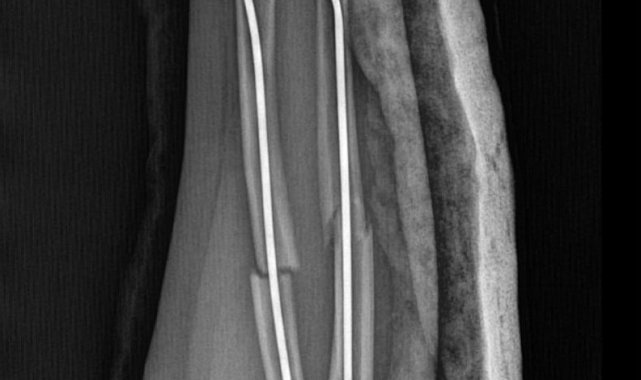

Olay, geçtiğimiz ay Büyükçekmece Tepecik'te bulunan bir ilkokulda meydana geldi. İddiaya göre 8 yaşındaki Y.K.Ş. okulda bir süredir kendisini rahatsız eden 9 yaşındaki çocuk tarafından darp edilerek kolu ikiye katlandı. Y.K.Ş.'nin 2'ye katlanan kolu 2 ayrı yerinden kırıldı. Öğretmenler Y.K.Ş.'nin ailesini arayarak, 'oğlunuz arkadaşıyla kavga etti duvara çarptı' denildi. Oğlunu okuldan alıp hastaneye götüren anne Songül Gökdemir, oğlunun kolunun 2 ayrı yerinden kırıldığını öğrenip ameliyata alınacağını duyduğunda büyük şok yaşadı. Konuyla ilgili anne Gökdemir savcılığa giderek şikayetçi oldu. Savcılıktan ise 'söz konusu Suça Sürüklenen Çocuğun yaşının 12'den küçük olduğu gerekçesi ile kovuşturmaya yer yoktur' kararı çıktı. Anne Gökdemir karara itiraz ederken mağdur Y.K.Ş. ise haftalardır okula gidemiyor. Eğitimi aksayan çocuğun 2 hafta sonra ise platinlerinin çıkarılması için yeniden ameliyata gireceği öğrenildi.

Yaşanan olayı anlatan Songül Gökdemir, " Arkadaşlarından darbe aldığını biliyordum. Ayrıca Eylül ayından bu yana bir arkadaşının onun kolunu kırmaya çalıştığını söyledi. Ben de 'arkadaşını öğretmene söyle' dedim. Bundan kaçıyordu. O gün de rehber öğretmenine bu arkadaşını şikayet ettiler. Ben işe gittim 1 saat sonra öğretmeni aradı. Oğlunuz arkadaşıyla birbirini itekledi kolunu duvara çarptı gelir misiniz ?' dedi. Kendi imkanımla hastaneye götürdüm. Okula gittiğimde de oğlum derste oturuyordu. Öğretmen ders işliyordu ambulans çağırılmamış. Hastanede kolunda 2 tane kırık olduğunu acilen de ameliyata girmesi gerektiğini öğrendim. 3 gün sonra ameliyata alındı. Kolundaki platinlerden dolayı her gün pansumanı var. 2 hafta sonra tekrar ameliyatı var" dedi.